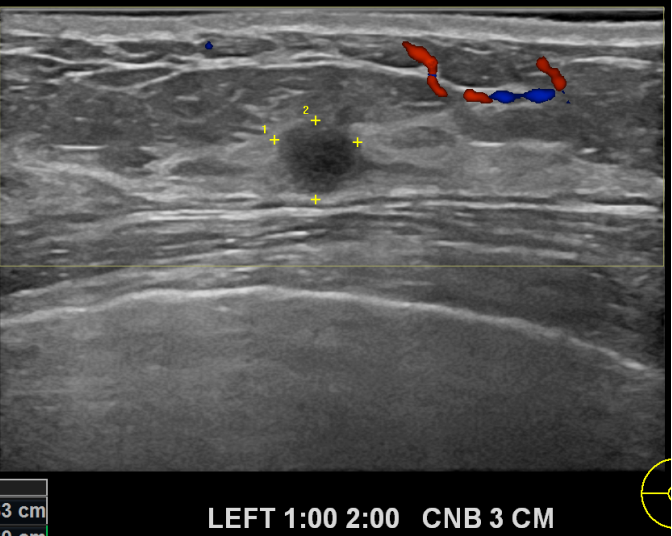

상기환자 외부검사이상으로  좌측조직검사를위해  내원하신 40대초반 여성분으로

좌측 조직검사 시행해 침윤성암으로 진단되었습니다